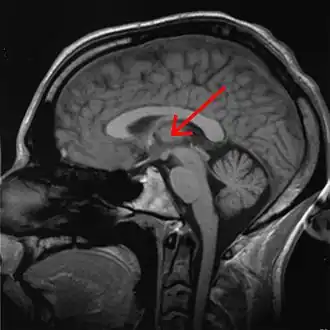

![]() Таламус человека на МРТ-снимке, отмечен стрелкой | |

Тала́мус, иногда — зри́тельные бугры (лат. thalamus; от др.-греч. θάλαμος «комната, камера, отсек») — отдел головного мозга, представляющий собой большую массу серого вещества, расположенную в верхней части таламической области промежуточного мозга хордовых животных, в том числе и человека. Впервые описан древнеримским врачом и анатомом Галеном. Таламус — это парная структура, состоящая из двух половинок, симметричных относительно межполушарной плоскости. Таламус находится глубже структур большого мозга, в частности коры или плаща. Под таламусом расположены структуры среднего мозга. Срединная (медиальная) поверхность обеих половинок таламуса одновременно является верхней боковой стенкой третьего желудочка головного мозга[1][2][3].

Таламус расположен вблизи центра мозга и входит в число структур таламической области промежуточного мозга. Он залегает под структурами большого мозга, но возвышается над структурами среднего мозга. Восходящие аксоны, исходящие из нейронов ядер таламуса, формируют пучки миелинизированных нервных волокон. Эти пучки нервных волокон обильно проецируются на различные области коры больших полушарий головного мозга во всех направлениях. Медиальная поверхность обеих половинок таламуса одновременно является верхней частью боковой стенки третьего желудочка головного мозга. Она соединена с соответствующей медиальной поверхностью противоположной половинки таламуса плоской полосой белого вещества. Эта полоса представляет собой пучок миелинизированных нервных волокон и называется межталамическим сращением, или промежуточной массой третьего желудочка, или срединной комиссурой (срединной спайкой) таламуса.